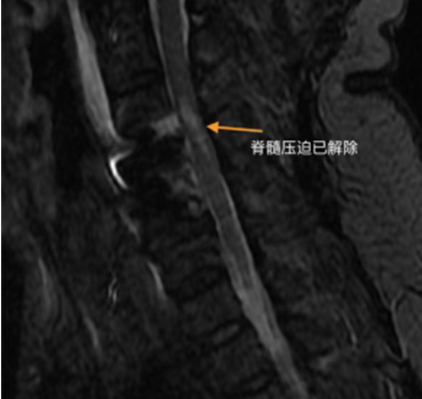

随后,患者相继出现头晕、头痛、呕吐及会阴区麻木。医疗团队紧急启动预案,查CT与MRI结果排除脑出血与急性脑梗死,最终确诊为颈3/4、颈4/5椎间盘突出压迫脊髓,伴脊髓部分变性,解除脊髓压迫为治疗关键。

面对紧急的病情,副院长、脊柱外科主任李世芳带领团队迅速评估,决定采用目前脊柱内镜微创技术——Endo-ACDF(内镜下前路颈椎间盘切除融合术),实施了C3/4、C4/5节段的内镜下减压融合手术。该技术通过天然颈前间隙建立微小通道,在水介质下通过内镜放大视野,能够精准地切除压迫脊髓的突出椎间盘,并植入椎间融合器稳定颈椎。其优势在于创伤极小,出血极少,能最大程度保护周围正常组织结构。

术后患者恢复迅速。术后第三日,在医护人员指导下已可实现生活自理,肢体肌力与感觉功能显著改善。此次从完全受限到重获活动能力的成功救治,这场与时间赛跑的急救,体现了团队对脊柱急危重症的快速诊断能力、应急决策水平与现代微创技术的有效应用,为保障区域民众脊柱健康提供了可靠技术支持。